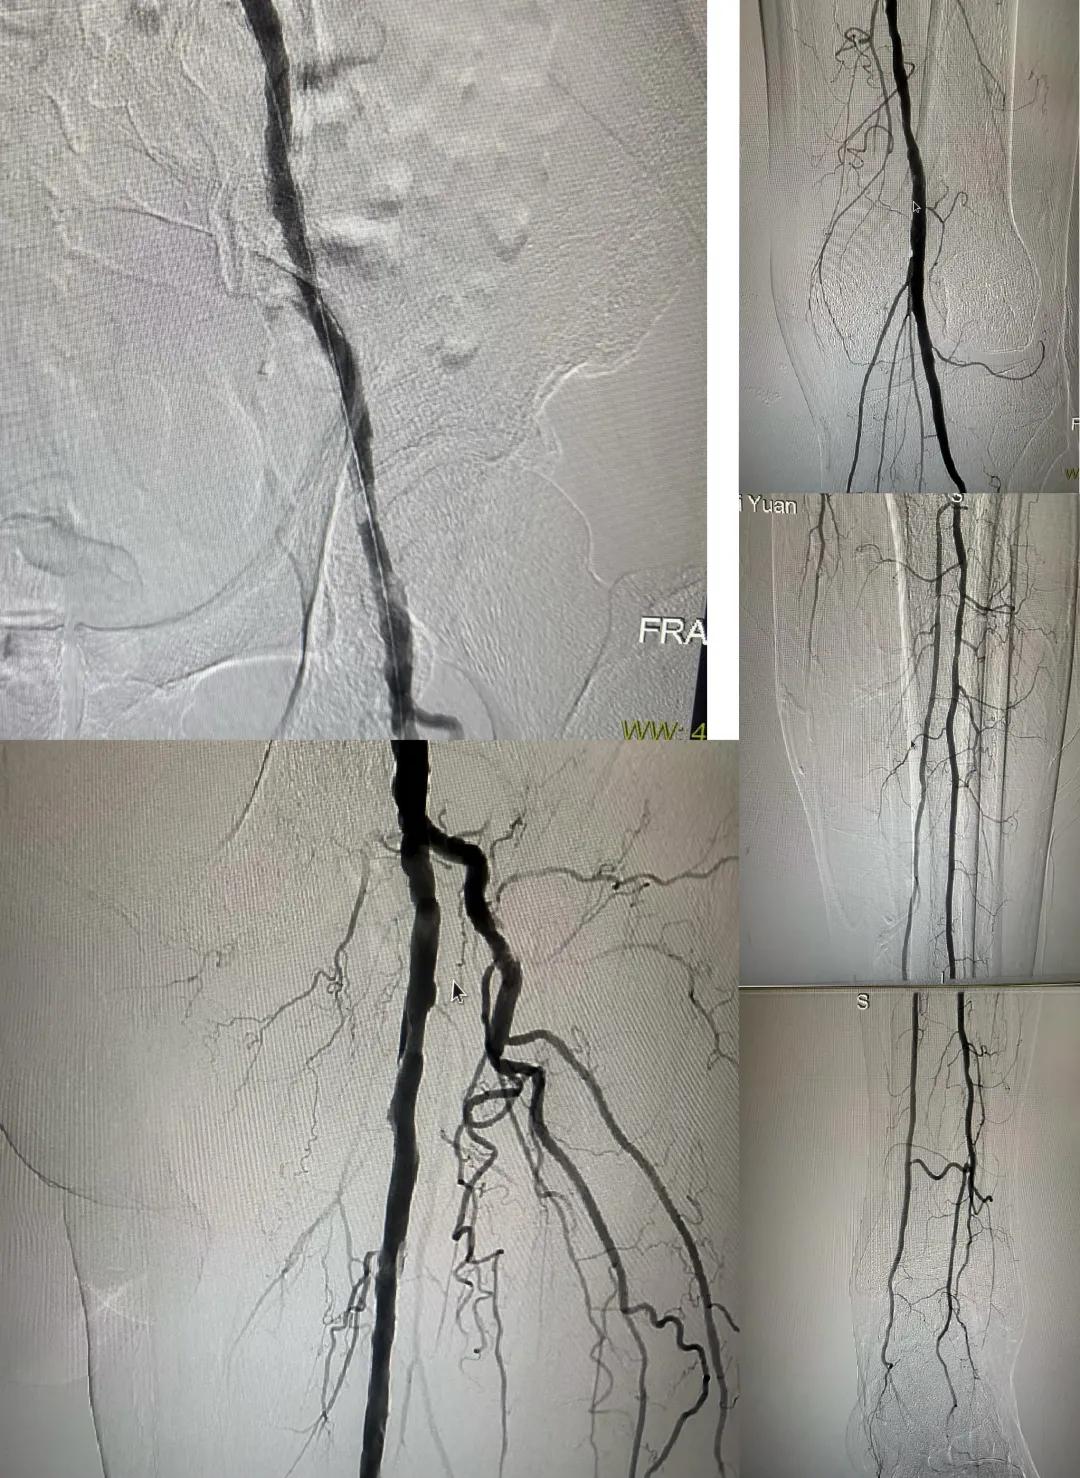

患者,男,73歲,約15天前出現(xiàn)左側(cè)腳面腫痛,間歇性跛行,左足第三足趾壞疽,遂來市中醫(yī)院就診,以“下肢動(dòng)脈硬化閉塞、糖尿病足壞疽、”收住外二科,評估患者病情后需實(shí)施左下肢球囊擴(kuò)張成形術(shù)。術(shù)中造影見患者左側(cè)髂動(dòng)脈、股淺動(dòng)脈階段性重度狹窄。經(jīng)外周球囊擴(kuò)張術(shù)后,再次造影見股淺動(dòng)脈、髂動(dòng)脈血流通暢,膝下及足部血流速度較前改善。

術(shù)后已疏通血管成像